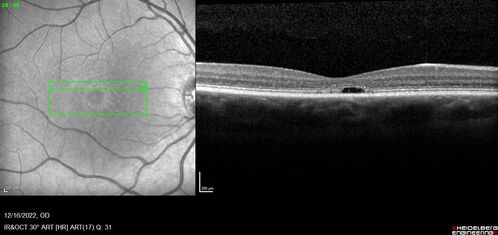

Stargardt Disease - Very Mild - 24 year old

This patient has 3 different ABCA4 mutations. His mother and sister have stargardts and his father has RP. His sisters images are also on Retinagallery.com